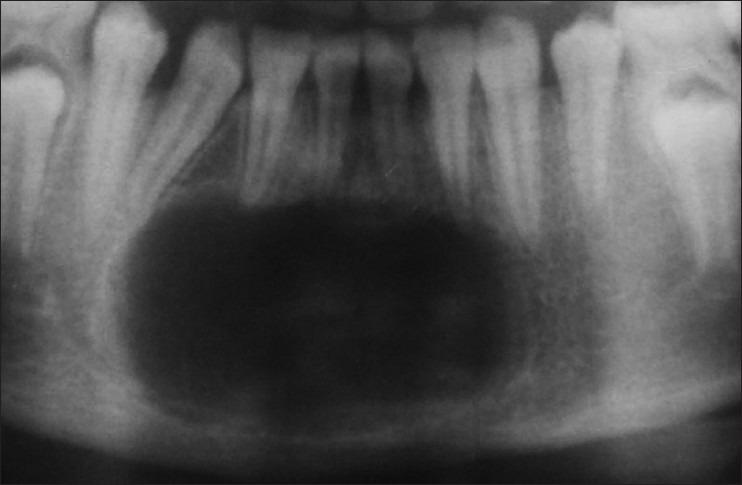

Nine different pathologies constituted the sample size of 17. A wide array of lesions was found to manifest similar signs and symptoms and radiographic findings namely ameloblastoma (three), adenomatoid odontogenic tumor (AOT, four), odontogenic keratocyst (OKC, three), ossifying fibroma (OF, two), idiopathic bone cavity (IBC, one), dentigerous cyst (DC, one), radicular cyst (RC, one), central giant cell granuloma (CGCG, one), and calcifying odontogenic cyst (COC, one).

9种不同病变构成了这17例的样本量。发现一系列病变表现出相似的体征、症状和影像学表现,即成釉细胞瘤(3例)、腺样牙源性肿瘤(AOT,4例)、牙源性角化囊肿(OKC,3例)、骨化性纤维瘤(OF,2例)、特发性骨腔(IBC,1例)、含牙囊肿(DC,1例)、根端囊肿(RC,1例)、中央巨细胞肉芽肿(CGCG,1例)和钙化牙源性囊肿(COC,1例)。